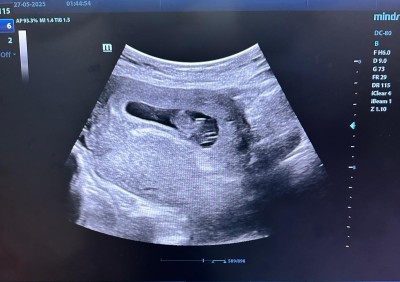

Kızlar cinsiyet merak ediyorum kese şekline göre tahmin yapılıyormuş  bizide yorumlarmısın

Gebelik haftası 10

Bebek erkek kese şekline göre

Keşe sekli.doktorun usg cihazini nasil ve nereden tutuşuyla alakali cinsiyetle alakasi yok cnm

Evet cinsiyetin sekille alakasi yok bu sekilde kiz di yuvarlak suan ki hamileligim erkek